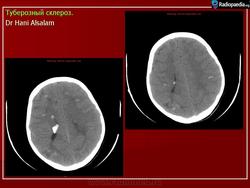

Факоматозы. Туберозный склероз, или синдром Бурневиля - Прингля 1. +

Туберозный склероз, или синдром Бурневиля - Прингля.

Туберозный склероз

Туберозный склероз (болезнь Бурневилля-Прингла, синдром Бурневилля - Брессау) - глиоз белого вещества мозга, проявляющийся в раннем детстве эпилептическими припадками (в 85%), олигофренией в сочетании с нараста­ющей пирамидной и экстрапирамидной симптоматикой, кожной патологией. В возрасте 4-6 лет на лице в форме бабочки в области носа обычно появляют­ся множественные желто-розовые или коричнево-красные узелки диаметром чуть больше 1 мм - аденомы Прингла, которые обычно признаются аденомами сальных желез, однако есть мнение и о том, что они представляют собой про­исходящую из нервных элементов кожи гамартрому.

Встречаются и аномалии развития извилин мозга в виде микро- и пахигирии. Заболевание чаще носит спорадический характер. Бляшки достигают диаметра 5-20 мм. В коре больших полушарий и мозжечка иногда могут быть обнару­жены пластинчатые тельца, напоминающие амилоид. Происходит дегенерация клеток коры. При КТ-исследовании головы нередко можно выявить кальцифика-ты и глиальные узелки в паравентрикулярной области, субэпендимарно вдоль на­ружных стенок боковых желудочков, в зоне межжелудочкового отверстия Мон­ро, реже - в мозговой паренхиме. На М РТ головного мозга в 60% выявляются гипотеденсивные очаги в одной или обеих затылочных долях, которые расце­ниваются как участки неправильной миелинизации (Козлов А.В., 2002).